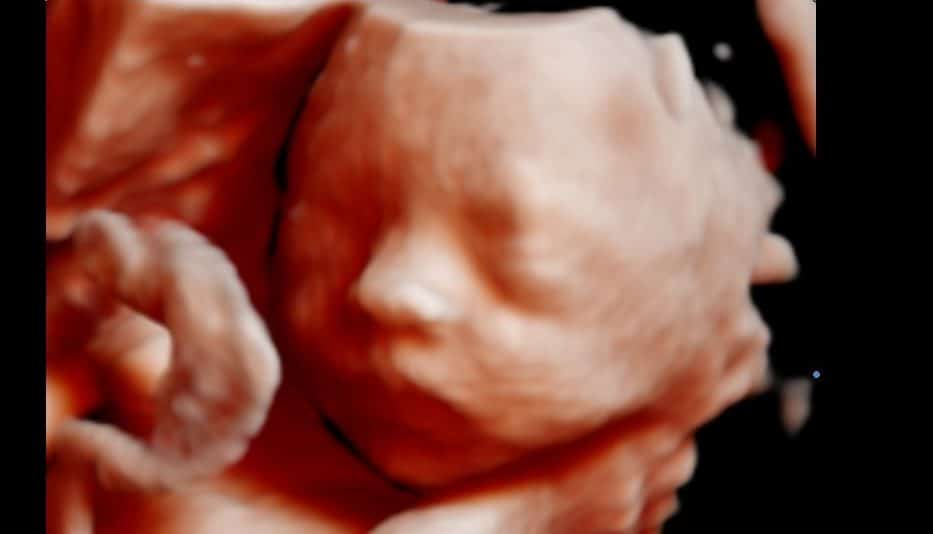

As melhores imagens da face são obtidas entre 26 a 29 semanas de gestação, pois neste período o feto já tem uma boa quantidade de tecido gorduroso em baixo da pele e ainda tem bastante líquido (o que é extremamente necessário para formação de imagens nítidas). Após 30 semanas podemos eventualmente obter imagens boas, entretanto isto torna-se muito difícil pois o espaço dentro do útero acaba tornando-se reduzido e o rosto fica a maior parte do tempo encoberto. Por isso nós recomendamos que você planeje a realização do exame entre 26 a 29 semanas de gestação.

Para obtermos uma imagem 3D/4D boa, inicialmete devemos ter uma imagem boa no exame de 2D. É importante frisar que o 3D não melhora a imagem do 2D, se a imagem estiver ruim no 2D provavelmente você não verá nada no 3D/4D. Para entender como deve estar a imagem veja as figuras abaixo. Na primeira imagem estamos vendo como idealmente seria a imagem em 2D para obtermos boas imagens 3D/4D. Observe três coisas importantes: (1) existe uma boa quantidade de líquido na frente da face fetal; (2) existe um bom contraste entre o líquido (preto) e a pele fetal (cinza); (3) não existem estruturas na frente da face (como membros fetais, cordão ou placenta).

Quando captamos a imagem 3D, o aparelho mostra inicialmente uma tela com 3 planos (horizontal, vertical e coronal) e a reconstrução 3D. Observe a área livre (escuro do líquido amniótico) diante da face fetal. Veja ainda que parte da face está bloqueada pela placenta (cinza) e a placenta é observada também na reconstrução 3D. É importante notar também que, mesmo que não identifiquemos nada na imagem do perfil, no momento que montamos a imagem 3D/4D poderemos observar alguma estrutura que não foi identificada na linha média.